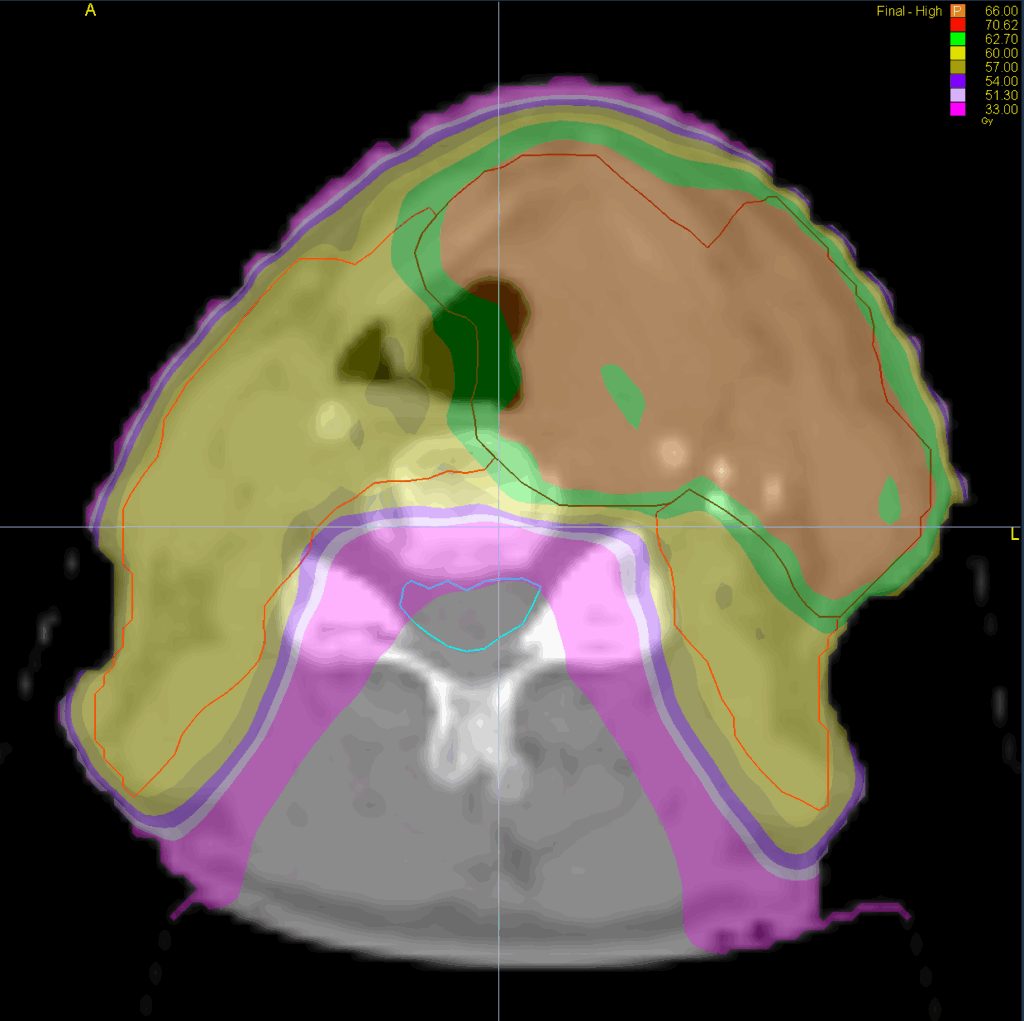

Treatment Plan Images

Fractionation / Protocol Used

66/60/54 Gy in 33 fractions

PTV(s) Volume, Length

967 cc, 21 cm